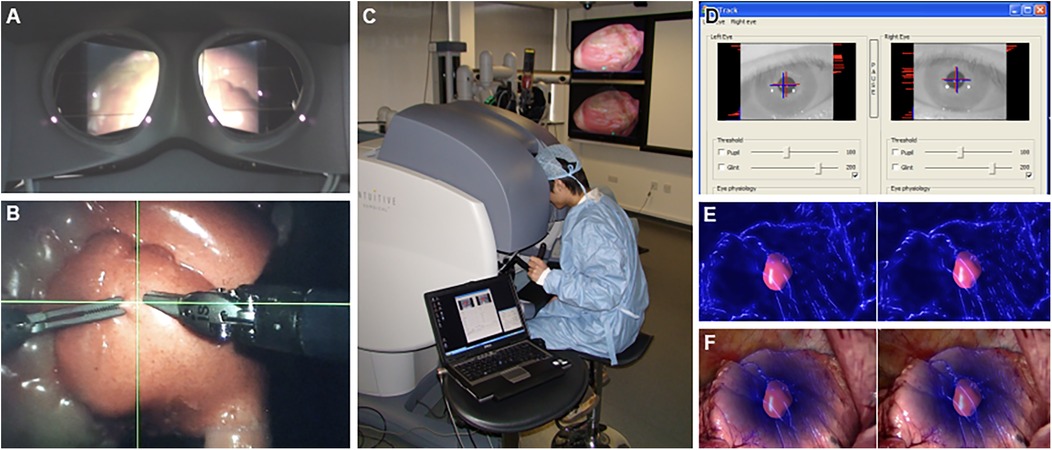

4.2.6 Surgical instrument tracking and hand-eye coordination

Systems like the one proposed by AbuSneineh and Seales (20) measure hand motions along with heart rate and body movements, including those of the arms, head, and eyes, using dedicated cameras (20). Yang et al. explored hand-eye coordination, hypothesizing that a gaze-contingent framework using binocular eye-tracking could aid robotic surgeries (Figure 8) (101). The results highlighted that enhanced surgical instrument manipulation and hand-eye coordination could be achieved by analyzing surgeons’ saccadic eye movements and ocular vergence (101).

Figure 8. Gaze-contingent perceptual docking. Yang et al. (101) presented the general concept of perceptual docking for robotic control. The aim was to investigate the potential use of perceptual docking for knowledge acquisition in robotic-assisted minimally invasive surgery. This figure represents the different aspects of the gaze-contingent perceptual docking. (A) The viewpoint of the surgeon using this system. (B) The surgical field and surgical instruments are shown intraoperatively. (C) External view of the surgeon and the system. (D) The binocular tracking of the eyes. (E and F) The application of augmented reality to gaze-contingent eye tracking, showing (E) nonphotorealistic augmented reality rendering and (F) fused with the original video. Used with permission from Yang G-Z, Mylonas GP, Kwok K-W, et al. Perceptual Docking for Robotic Control, in: T. Dohi, I. Sakuma and H. Liao (Eds.), Medical Imaging and Augmented Reality, Berlin, Heidelberg: Springer Berlin Heidelberg. 2008;21–30.